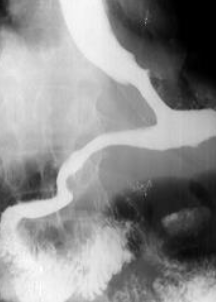

Achalazia cardiei